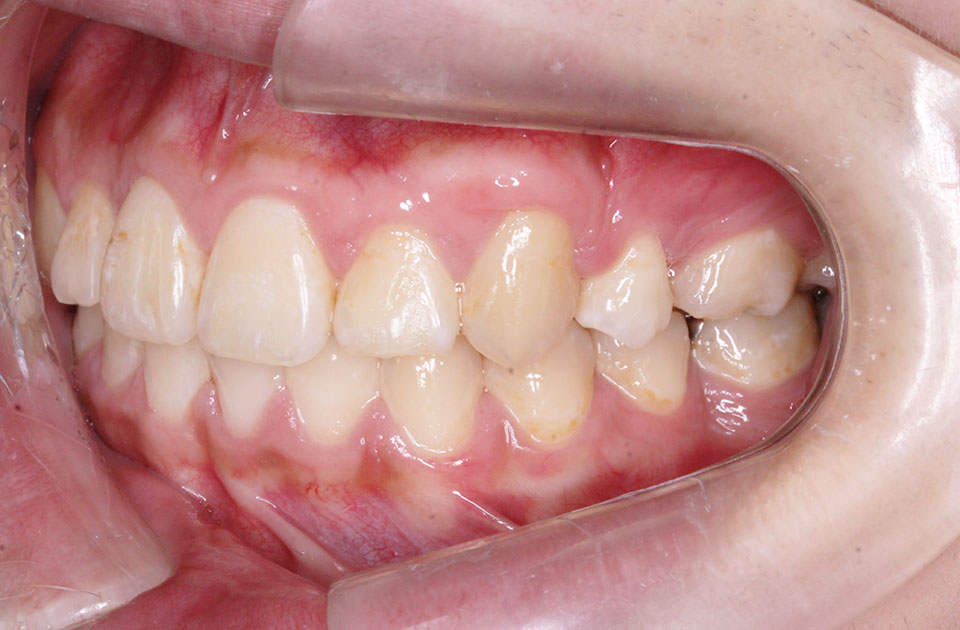

矯正後

矯正後 右側

矯正後 左側